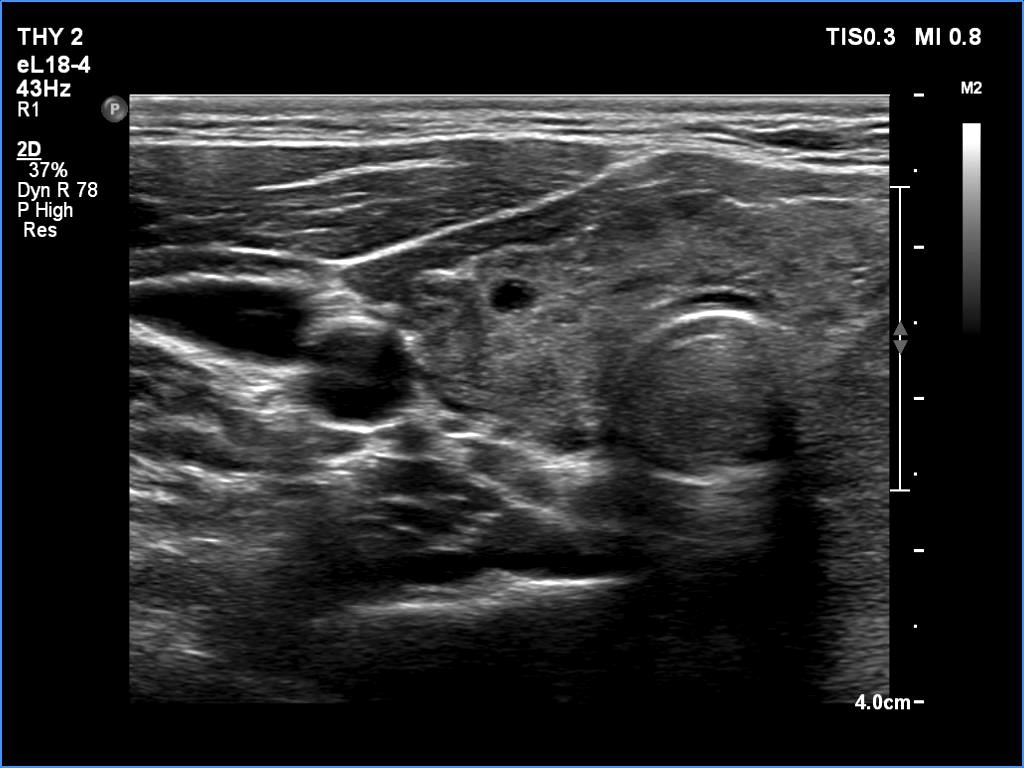

Second examination - five years later (second row of images)

Clinical presentation: The patient came to follow-up because she noticed a slow increase in the size of the left lobe.

Palpation: a firm nodule in the left lobe.

Laboratory tests: TSH 0.98 mIU/L.

The dimensions of the nodule in the left lobe were 40x25x43 mm, width, depth, length, respectively, the volume of the lesion was 22.5 mL.

Aspiration cytology resulted in follicular tumor. Surgery was advised.